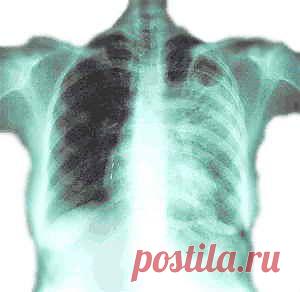

Мой дед в далекие послевоенные го­ды заболел туберкулезом.